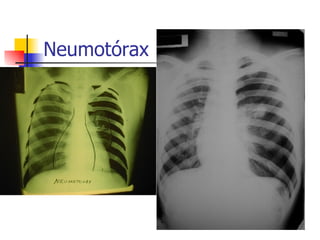

Neumotórax Aire en el espacio pleural  Penetración de la pared torácica Trauma Iatrogenico Fuga del parenquima pulmonar Enfermedad pulmonar: primario o secundario Via aérea barotrauma

Neumotórax espontáneo Primario 5:1 hombres, edad 20-40 Bulas subpleurales apicales 80-100% Paciente alto, delgado  Predisposición génetica Secundario EPOC, Bulas, Asma, Tuberculosis, Sida (pneumocistis carini), catamenial

Neumotórax espontáneo signos y síntomas Dolor torácico agudo y disnea Síndrome de Neumotórax Movilidad disminuida Frémito vocal abolido Percusión timpánica Ruido respiratorio abolido

Neumotórax